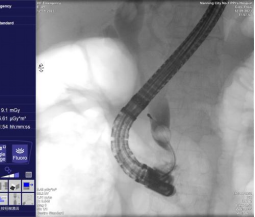

4、内镜下逆行胰胆管造影术(ERCP)

广西首例十二指肠乳头癌ERCP治疗单位,结石清除率>95%。由于ERCP不用开刀,创伤小,手术时间短,并发症较外科手术少,住院时间也大大缩短,深受患者欢迎。适应于:1. 胆道梗阻引起的黄疸;2. 胰腺或胆道疾患(如结石、肿瘤、硬化性胆管炎等)。

胆总管结石造影所见 网篮取出结石

十二指肠乳头癌 十二指肠乳头插管

胆管金属支架置入过程 金属支架置入术后